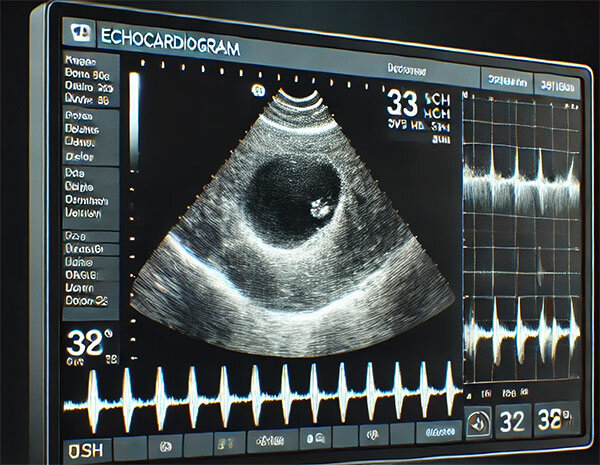

اکو قلبی یا اکوکاردیوگرافی (Echocardiography) یک روش تصویربرداری پزشکی غیرتهاجمی است که برای بررسی ساختار و عملکرد قلب و دریچههای آن استفاده میشود. این آزمایش با استفاده از امواج صوتی با فرکانس بالا (اولتراسوند) انجام میشود و تصاویر دقیقی از قلب در حالت زنده و در زمان واقعی ارائه میدهد. اکو قلبی به پزشکان کمک میکند تا بیماریهای قلبی را تشخیص دهند، شدت آنها را ارزیابی کنند و روند درمان را پایش نمایند.

تولید تصاویر:

دستگاه بازتاب امواج را پردازش کرده و تصاویر دقیقی از قلب روی مانیتور نمایش میدهد. پزشک این تصاویر را برای ارزیابی ساختار و عملکرد قلب بررسی میکند. -

این روش رایجترین نوع اکو قلبی است. در این حالت، پروب روی قفسه سینه قرار میگیرد و تصاویر بهصورت مستقیم از طریق دیواره قفسه سینه گرفته میشوند. این روش برای اکثر بیماران کافی است و اطلاعات جامعی درباره قلب ارائه میدهد.